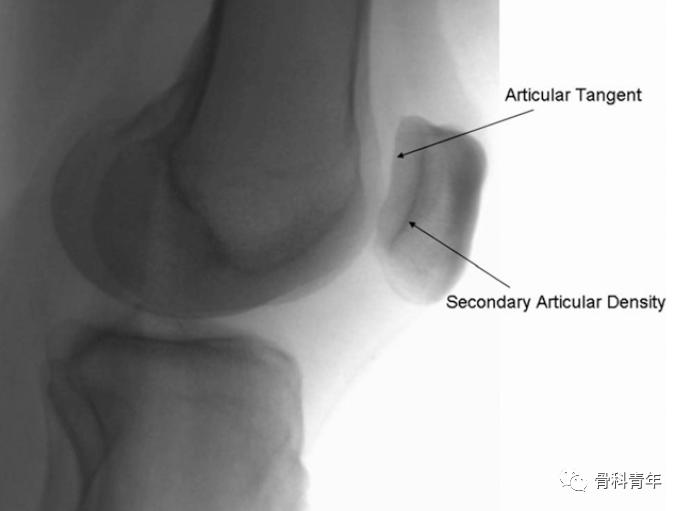

影像上,髌骨内外侧关节面均为倾斜面,在正常侧位上无法有效评估。

在常规膝关节侧位上,髌骨内外侧关节面重叠,显示不清

有学者研究表明,在髌骨外旋24°可在侧位上评估外侧关节面复位情况,内旋34°可以评估内侧关节面情况。